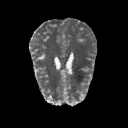

The goal of unsupervised anomaly segmentation (UAS) is to detect the pixel-level anomalies unseen during training. It is a promising field in the medical imaging community, e.g, we can use the model trained with only healthy data to segment the lesions of rare diseases. Existing methods are mainly based on Information Bottleneck, whose underlying principle is modeling the distribution of normal anatomy via learning to compress and recover the healthy data with a low-dimensional manifold, and then detecting lesions as the outlier from this learned distribution. However, this dimensionality reduction inevitably damages the localization information, which is especially essential for pixel-level anomaly detection. In this paper, to alleviate this issue, we introduce the semantic space of healthy anatomy in the process of modeling healthy-data distribution. More precisely, we view the couple of segmentation and synthesis as a special Autoencoder, and propose a novel cycle translation framework with a journey of 'image->semantic->image'. Experimental results on the BraTS and ISLES databases show that the proposed approach achieves significantly superior performance compared to several prior methods and segments the anomalies more accurately.